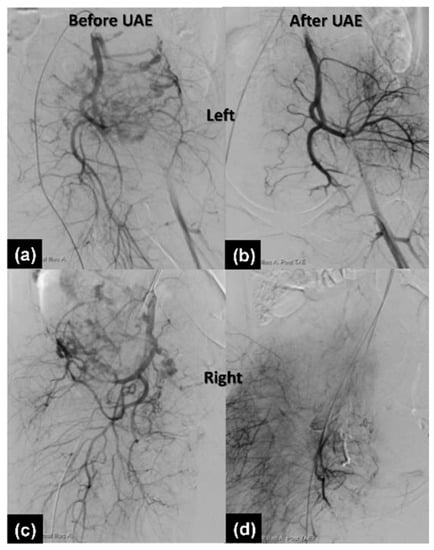

2.2.3. Therapeutic Intervention

2.2.4. Follow-Up and Outcomes